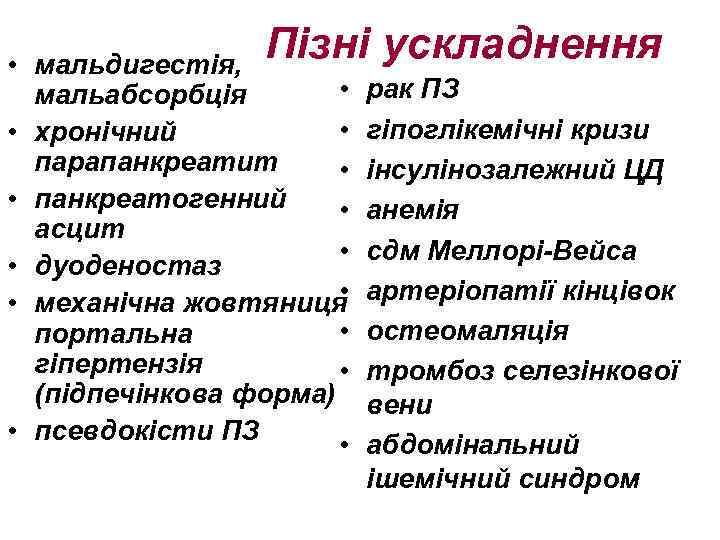

Пізні ускладнення • мальдигестія, • мальабсорбція • • хронічний парапанкреатит • • панкреатогенний • асцит • • дуоденостаз • • механічна жовтяниця • портальна гіпертензія • (підпечінкова форма) • псевдокісти ПЗ • рак ПЗ гіпоглікемічні кризи інсулінозалежний ЦД анемія сдм Меллорі-Вейса артеріопатії кінцівок остеомаляція тромбоз селезінкової вени абдомінальний ішемічний синдром

Пізні ускладнення • мальдигестія, • мальабсорбція • • хронічний парапанкреатит • • панкреатогенний • асцит • • дуоденостаз • • механічна жовтяниця • портальна гіпертензія • (підпечінкова форма) • псевдокісти ПЗ • рак ПЗ гіпоглікемічні кризи інсулінозалежний ЦД анемія сдм Меллорі-Вейса артеріопатії кінцівок остеомаляція тромбоз селезінкової вени абдомінальний ішемічний синдром